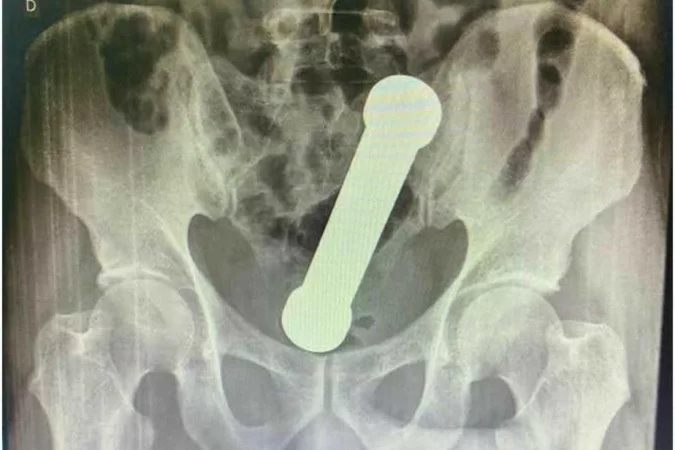

Após exames físicos, foram solicitados hemograma, estudo bioquímico e radiografia da região abdominal. A radiografia apresentou a presença de um corpo estranho em forma de haltere de ginástica em “localização aproximada na transição retossigmóide” — entre a parte terminal do intestino e parte inicial do reto. “Devido ao quadro clínico estável do paciente, sem sinais de perfuração, optou-se pela abordagem retal inicial”, relatou a publicação.